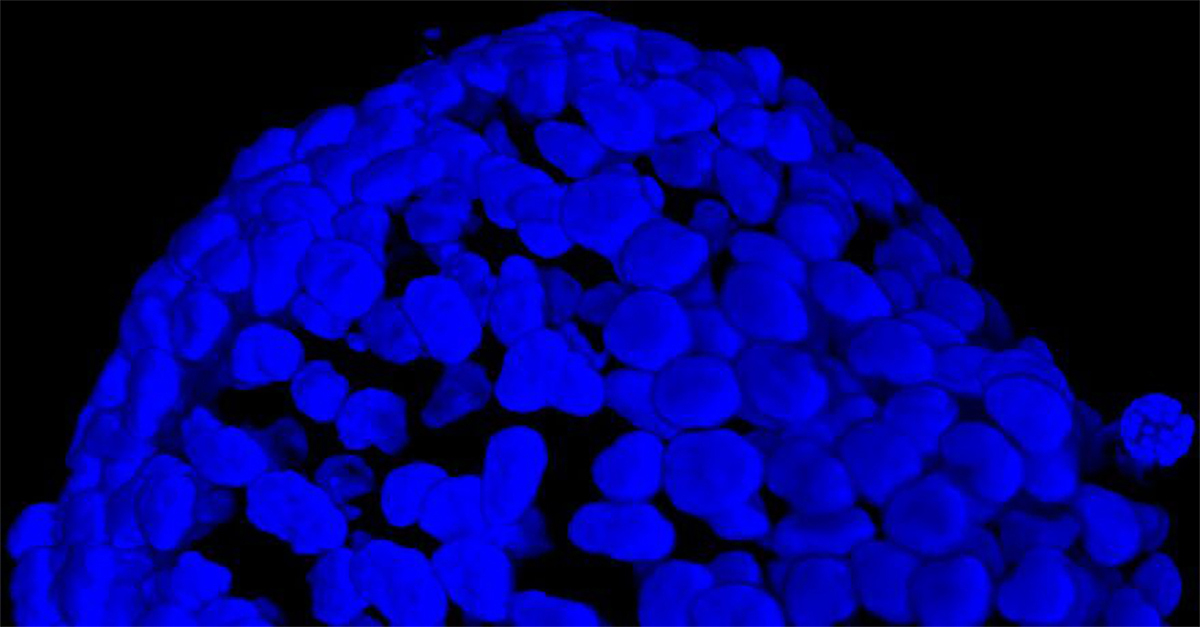

To better appreciate the 3D cellular organization, in Figure C we show a volume view (120 um thickness) of the same spheroid acquired with both objectives, showing the staining even in the deeper regions of the 3D cancer spheroid. Finally, in Figure D, a 3D movie of the whole spheroid acquired with the 25x silicone oil objective is shown.

Figure C 3D tumor spheroids: 3D volume view of a spheroid acquired with 20x air objective (LEFT) and 25x silicone oil objective (RIGHT). Living cells are marked with Calcein (green) and dead cells with PI (red). Nuclei are stained with Hoechst (blue). Scale bar along Z-axis: 120 um. These images were acquired with CrestOptics X-Light V3 spinning disk.